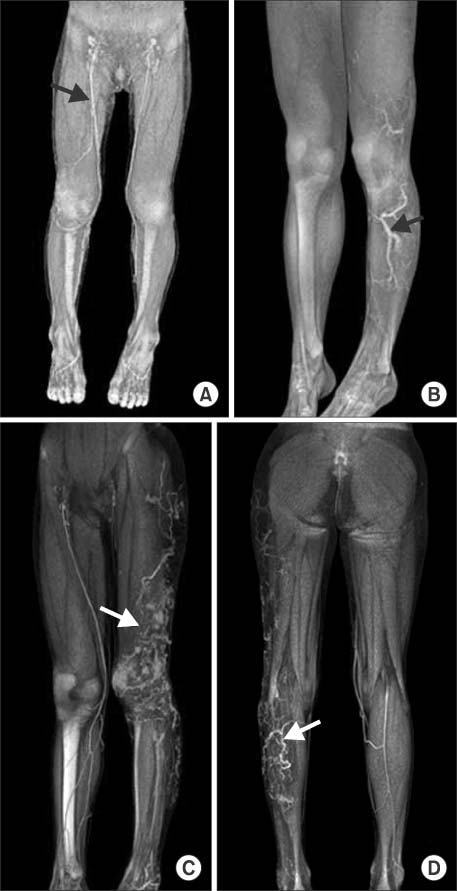

(A) A 3-year-old child has dilatation of the right great saphenous vein (arrow). (B) A 15-year-old child has enlargement of great and small saphenous vein (arrow). (C, D) A 7-year-old child has venous malformation of left lower leg (arrow). She has prominent venous dilatation of the thigh and knee portion (arrow).

Fig. 1 (A) A 3-year-old child has dilatation of the right great saphenous vein (arrow). (B) A 15-year-old child has enlargement of great and small saphenous vein (arrow). (C, D) A 7-year-old child has venous malformation of left lower leg (arrow). She has prominent venous dilatation of the thigh and knee portion (arrow).